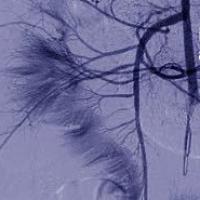

With NIH support, scientists across the United States and around the world conduct wide-ranging research to discover ways to enhance health, lengthen life, and reduce illness and disability. Groundbreaking NIH-funded research often receives top scientific honors. In 2022, these honors included two NIH-supported scientists who received Nobel Prizes. Here’s just a small sample of the NIH-supported promising medical findings in 2022. For more health and medical research findings from NIH, visit NIH Research Matters.